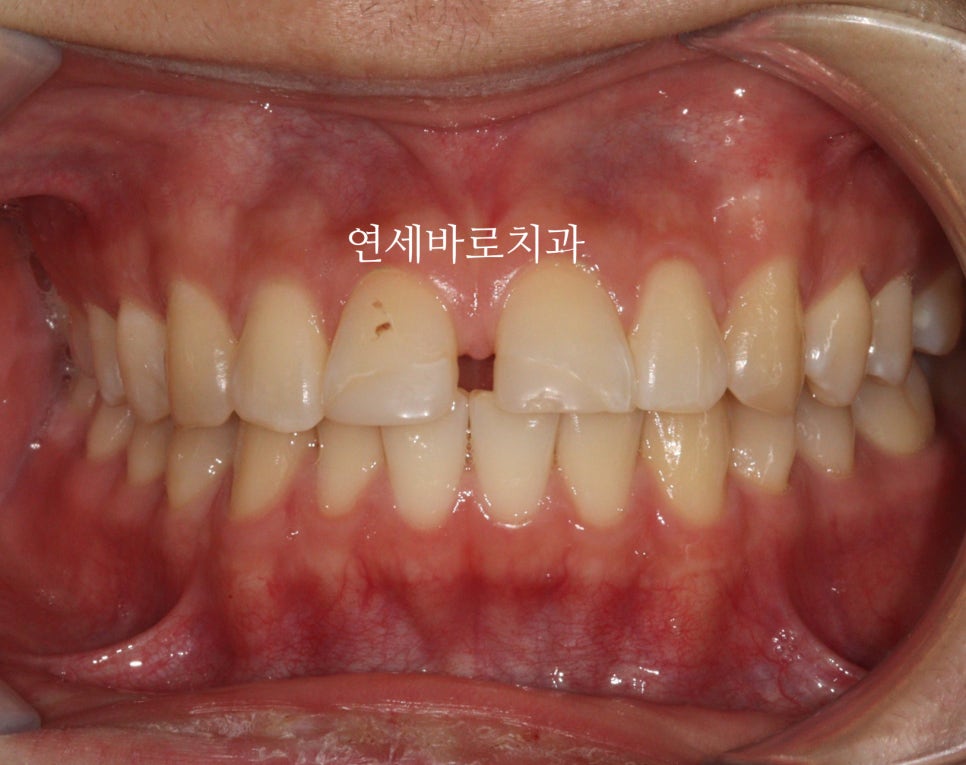

벌어진 치아 치료, 레진·라미네이트 vs 교정치료 비교

그런 상태인 치아를 양옆을 크게 만드는 레진, 라미네이트로 치료를 한다면 당장은 예쁠 수 있지만 다시 벌어진답니다.

그리고 당장 예쁠 수 있겠지만 이라고 말했지만 아닐 수 있어요

당장 치아가 커지거든요

여기서 저 공간을 레진 등으로 매꾼다면 더 커지는 치아의 사이즈로 인해 심미적이지 못할겁니다.

벌어진 치아는 대부분 시간이 지나면서 점점 벌어지게 되는 경우가 많습니다. 이런 상태에서 레진이나 라미네이트로 양옆을 크게 만드는 치료를 하면 당장은 공간이 메워지지만, 치아가 계속 벌어지는 경향이 있어 다시 틈이 생길 수 있고, 치아 크기가 커져 심미적이지 못할 수 있습니다.